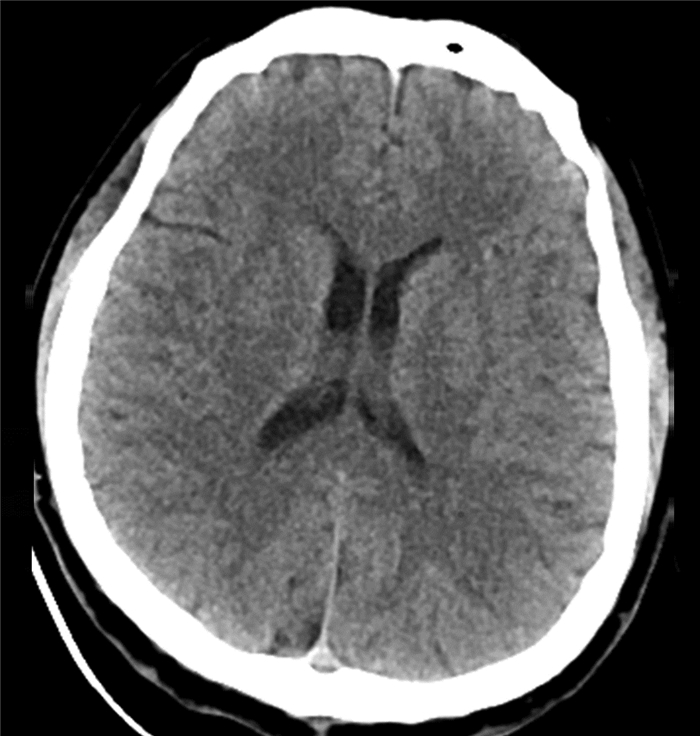

Endoscopic treatment of gastroesophageal varices complicated by posterior reversible encephalopathy syndrome: A case report

Tingting YU, Shanshan JIANG, Mengran ZHU, Yun BAI

2022, 38(1): 177-179. DOI: 10.3969/j.issn.1001-5256.2022.01.030

Abstract(807) HTML (197) PDF (3069KB)(54)

Abstract: